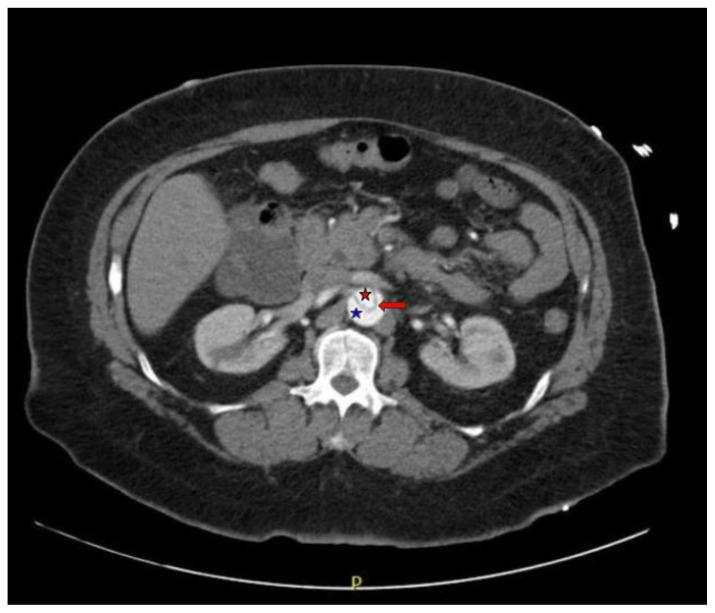

Acute aortic dissection is a life-threatening event caused by separation of the aortic layers that requires prompt management and surgical consultation. We present the case of a 53-year-old male who developed acute, severe chest pain radiating to his back at a community hospital and was transferred to a tertiary center for definitive surgical management. The patient's aortic dissection was diagnosed via computed tomography angiography. He was started on rate-control and blood pressure medications, and was admitted emergently to the operating room. Emergency physicians should obtain immediate surgical consultation, promptly start medications for rate and blood pressure control, and administer analgesia in order to stabilize their patient and decrease the shear forces that would further propagate an aortic dissection.

急性主动脉夹层是一种由主动脉各层分离引起的危及生命的事件,需要及时处理并进行外科会诊。我们报告一例53岁男性病例,该患者在社区医院出现急性、严重的胸痛并放射至背部,随后被转至三级中心进行确定性手术治疗。患者的主动脉夹层通过计算机断层扫描血管造影术确诊。他开始接受心率控制和血压药物治疗,并紧急送入手术室。急诊医生应立即进行外科会诊,迅速开始使用控制心率和血压的药物,并给予镇痛治疗,以稳定患者病情并降低会进一步加重主动脉夹层的剪切力。